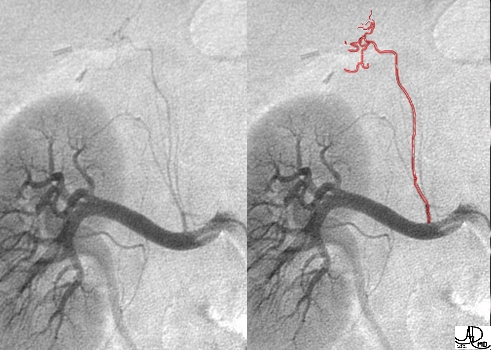

Arterial Supply – Imaging |

This image reflects the right renal artery with the capsular branch arising from within 2 cm. from the aortic origin. The inferior adrenal artery is overlayed in red and can be seen terminating in a tuft of vessels at the adrenal gland. Courtesy of: Ashley Davidoff, M.D. |

In this instance the middle and superior adrenal arteries can be seen supplying the right adrenal gland.(yellow overlay) Courtesy of: Ashley Davidoff, M.D. |

This image depicts the relationship of the middle and superior adrenal arteries with the adrenal gland and the superior pole of the right kidney. Courtesy of: Ashley Davidoff, M.D. |